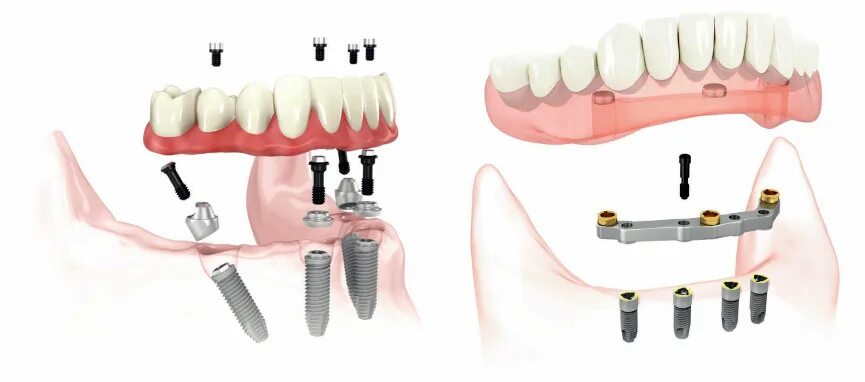

Поставить 4 зуба